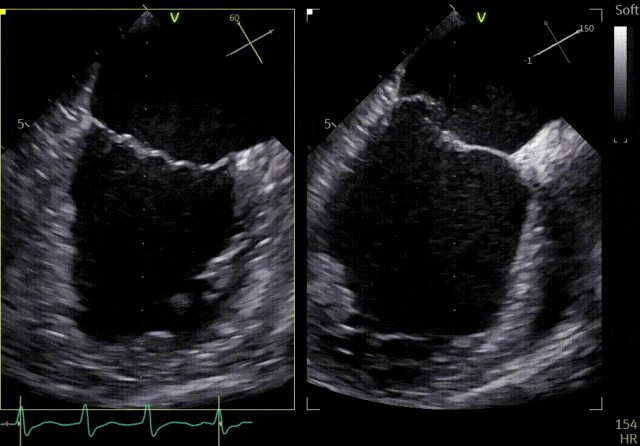

患者为41岁男性,心脏彩超提示:二尖瓣P2脱垂合并房性机制,左心扩大、瓣环扩张,反流主要来源于2区。反流宽度:20mm,2区瓣叶长度:2.2/1.3cm,AP径:43mm,瓣口面积:6.0cm²。

术前

X-plane 2区

X-plane 2区彩色

3D

3D彩色